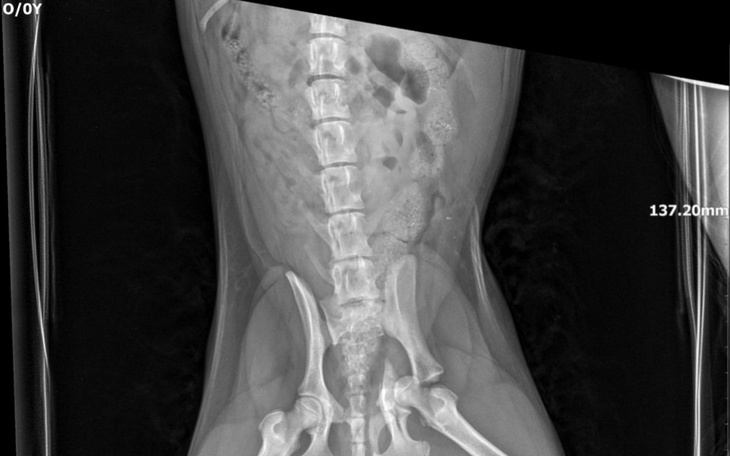

Sunia miała wypadek i ma połamaną miednicę,ale walczymy o to by mogła jeszcze stanąć na własnych łapach. Ten mokry nos ma jeszcze wiele dołków do wykopania.

Operacja jest niezbędna i pomimo moich najlepszych starań, potrzebujmy pomocy osób z mojego otoczenia, aby opłacić część jej rachunków weterynaryjnych